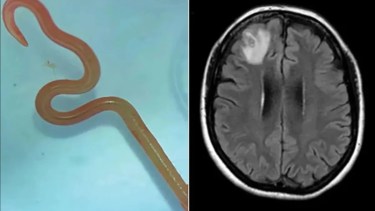

Según el diario The Canberra Times, la cirujana Hari Priya Bandi le extrajo una parásito vivo, que medía unos 8 centímetros.

Ya en el hospital de Canberra se revelaron anomalías en el cerebro, lo que derivó en la cirugía en donde se extrajo al gusano. “El gusano se movía con vigor. Todos nos sentimos un poco asqueados”, explicó Bandi tras el sorprendente hallazgo.

El gusano no se parecía a ningún tipo de lombriz intestinal conocida que podría causar invasión y enfermedades neurológicas, por lo que los médicos consultaron a un experto en parásitos de la Organización de Investigación Científica e Industrial del Commonwealth, quienes confiaron que se trataba de un Ophidascaris robertsi.